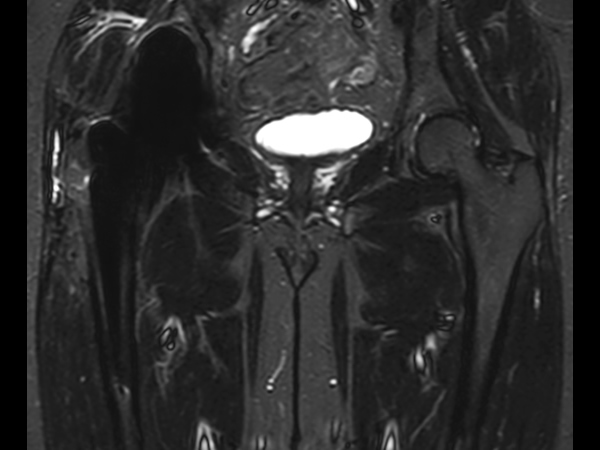

Hip imaging with metal implant

Used Solution

**Only for use with MR Safe or MR Conditional Implants by strictly following the Instructions for Use.